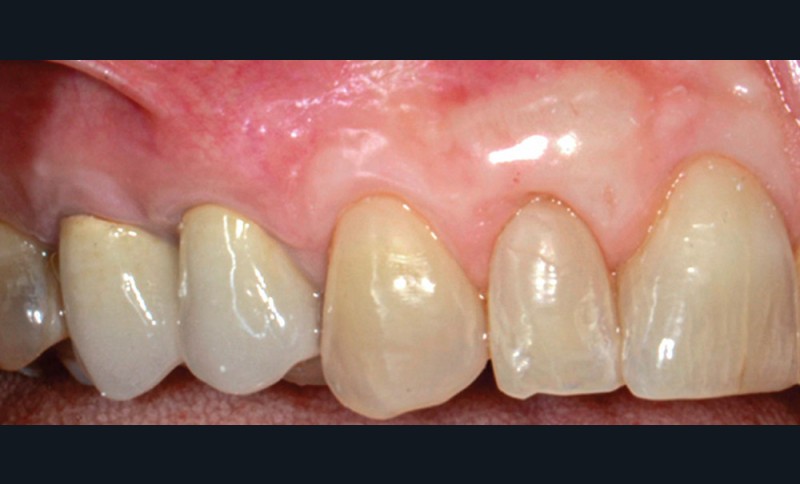

Le lambeau coronairement avancé multiple (MCAF), proposé par Zucchelli et de Sanctis (2 000), est devenu la procédure de couverture radiculaire la plus largement utilisée pour les défauts de récession multiples. Il présente une évolution technique et esthétique du lambeau d’avancée coronaire avec incision de décharge qui n’est désormais plus recommandé. Ce lambeau est défini par son tracé d’incision autour de la récession principale et par son épaisseur en partielle-totale-partielle (« Split-Full-Split »).

Cette technique, sans greffon de conjonctif associé, permet un taux de recouvrement complet de 80 %. La préservation de l’épaisseur du lambeau et la présence du périoste semble jouer un rôle fondamental dans l’obtention du recouvrement complet.